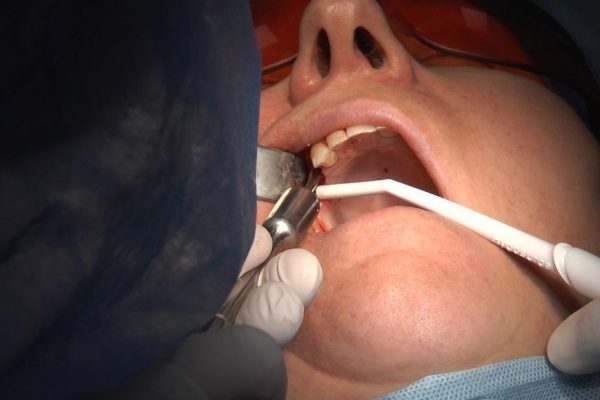

W ostatni weekend czerwca 2018 roku kursanci II Sezonu Preludium Implantologii odbyli piątą, finałową sesję, która w całości podporządkowana była praktyce. W ciągu dwóch dni zabiegowych Lekarze uczestniczący w szkoleniu przeprowadzili szereg zabiegów pod kierunkiem dr n.med. Violetty Szycik. Wszczepili 17 implantów oraz przeprowadzili ekstrakcje i zabiegi regeneracyjne kości. Zabiegi były wykonywane także w sedacji dożylnej z udziałem specjalisty anestezjologii i intensywnej terapii dr Jolanty Grzybowskiej. Preludium implantologii to nowy program edukacyjny dla adeptów implantologii stomatologicznej, którego celem jest wprowadzenie do implantologii poprzez pozyskanie wiedzy w szerokim zakresie i uwzględnieniem szczegółów mających decydujące znaczenie dla powodzenia leczenia implantologicznego. Ale tak jak wszystkie szkolenia w Instytucie Vivadental, w tym wiodące Practiculum Implantologii, zorientowane jest na praktyce i samodzielnym wykonywaniu zabiegów pod kierunkiem Mentora. To najlepsza edukacja w medycynie zabiegowej, a zarazem najlepszy start do implantologii.